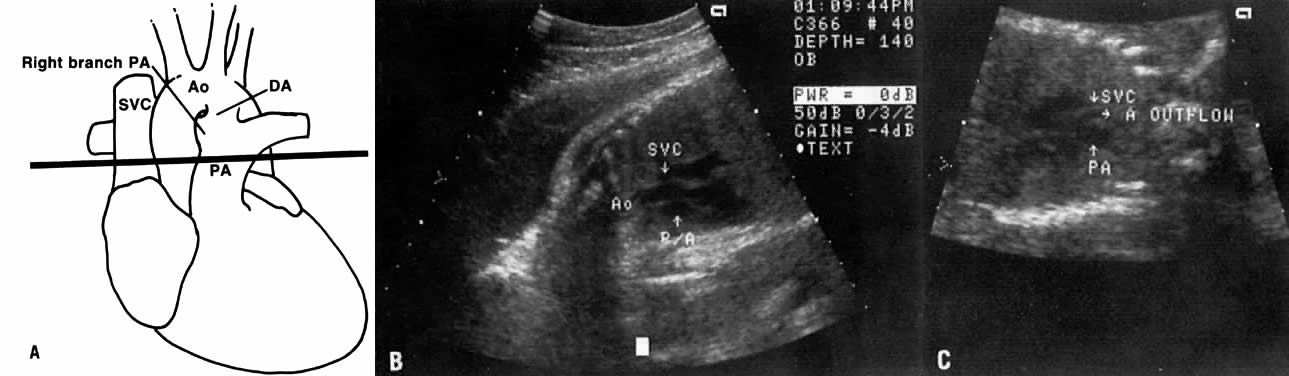

Great Vessel View

The great vessel view depicts the relatively parallel relationship of the superior vena cava, aorta, and pulmonary arteries after the latter two cross each other (Fig. 8). Clear visualization of this plane indicates that the crossing of the aorta and pulmonary artery is normal and virtually rules out transposition of the great vessels. Aortic or pulmonary stenosis also can be recognized in this view.

Fig. 8. A. Schematic drawing of the crossing of the pulmonary artery (PA) and the aorta (Ao) . Note how the branch of the pulmonary artery passes below the aorta (see Fig. 7). The black line is the plane that shows the great vessel view (GVV) depicting the almost parallel relationship between the superior vena cava (SVC), PA, and Ao. B. Echogram of the GVV showing the almost parallel relationship between the SVC, P/A, and Ao. C. Echogram of GVV showing aortic stenosis with very small aortic outflow (A outflow) and a normal-sized pulmonary artery. (DA = ductus arteriosus)

In truncus arteriosus, the pulmonary artery is not clearly depicted by ultrasound. Instead, the aortic outflow tract is large and the aorta is overriding.

The great vessel view also allows a comparative measurement of the two arteries a short distance beyond the valvular level; the measurements should be obtained from the inner aspects of these arteries. Normally the ratio of pulmonary artery: aorta has a mean value of 1.09 (range = 0.75 to 1.43) and is independent of gestational age.24